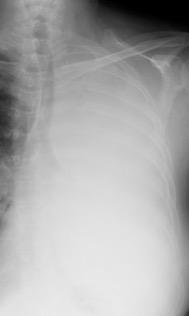

Visible en radiografías en decúbito supino de los pacientes con neumotórax por la acumulación de aire en el seno costofrénico.

“Deep sulcus sign”. Seno costofrénico aumentado en anchura y profundidad